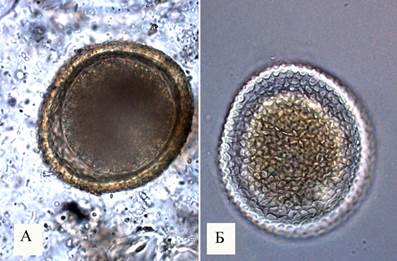

Микрофотографии яиц гельминтов Toxocara canis

Раздел: Фотоэссе